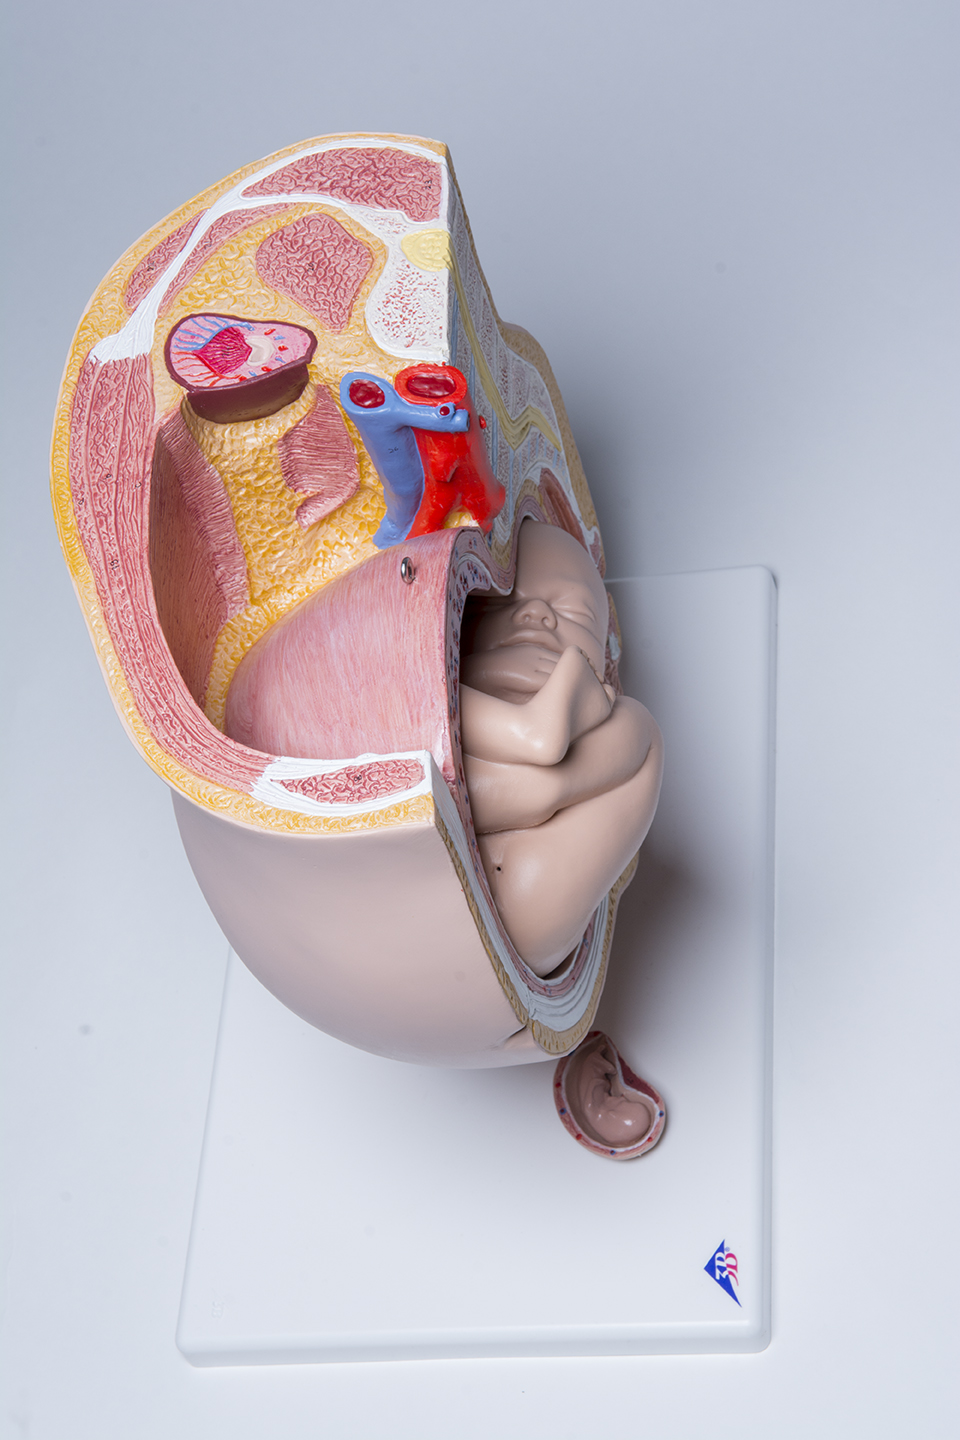

Pelvic Anatomy Pregnancy Model

This anatomy pregnancy model is a representation of a median section through the female pelvis at 40 weeks pregnant with a removable fetus. Study the normal position of child before birth with this model plus the human reproductive and urinary systems. A uterus with embryo in 3rd month of pregnancy is mounted on base for added detail. The realistic and high quality female pelvis includes the female genital organs and other important anatomical details. This pregnancy female pelvis is a great addition to any anatomy classroom or clinician’s office to educate about the effects of pregnancy.

This pelvic anatomy pregnancy model allows the clinician to easily explain what is taking place internally during pregnancy and how it affects surrounding organs, muscle and bone. This will enable to clinician to point out the many issues that can arise from childbirth and what can be done proactively to prevent them.